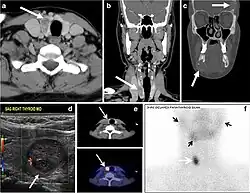

- Fig. 6. A 61-year-old female patient with locally aggressive PTC. an Enhanced axial CT scan of the neck demonstrates a heterogeneous infiltrative thyroid mass. This mass diffusely involves the entire gland and circumferentially encases the trachea with involvement of bilateral tracheoesophageal grooves (white arrows). b, c Additional axial cranial images show right cricoid cartilage destruction (black arrows in b), right thyroid cartilage destruction (black arrow in c), right vocal cord paralysis (white arrows in b), and bilateral cervical lymphadenopathy (arrowheads).[1]

The radiologist must evaluate the central structures draping the thyroid gland including the trachea, oesophagus, larynx, and pharynx, as well as the recurrent laryngeal nerve. Invasion is suspected if the thyroid mass abuts the airway or oesophagus for more than 180 degrees. Luminal deformity, mucosal thickening and mucosal focal irregularity are more specific indicators of invasion. Obliteration of the fat planes of the tracheoesophageal groove in three axial images and signs of vocal cord paralysis are indicative of recurrent laryngeal nerve invasion. Invasion of these central structures meets the criteria for T4a disease (Figs. 5 and and6)6).[1]

Arterial invasion constitutes T4b disease, which may preclude curative surgery. More than 180 degrees of arterial encasement is suggestive of invasion, however, arterial deformity or narrowing is much more suspicious for invasion. The carotid artery is the most commonly involved artery; however, the mediastinal vessels should also be examined. Encasement of the carotid artery or mediastinal vessels for more than 270 degrees is unlikely to be resectable. On the other hand, occlusion or effacement of the internal jugular vein can occur without invasion and does not influence surgical resectability or staging. Asymmetry of the strap muscle and the tumour abutting its external surface are signs of an invasion. However, invasion of the pre-vertebral musculature is more challenging, as a large lesion can compress the muscle without invasion (Figs. 5 and and6)6).[1]